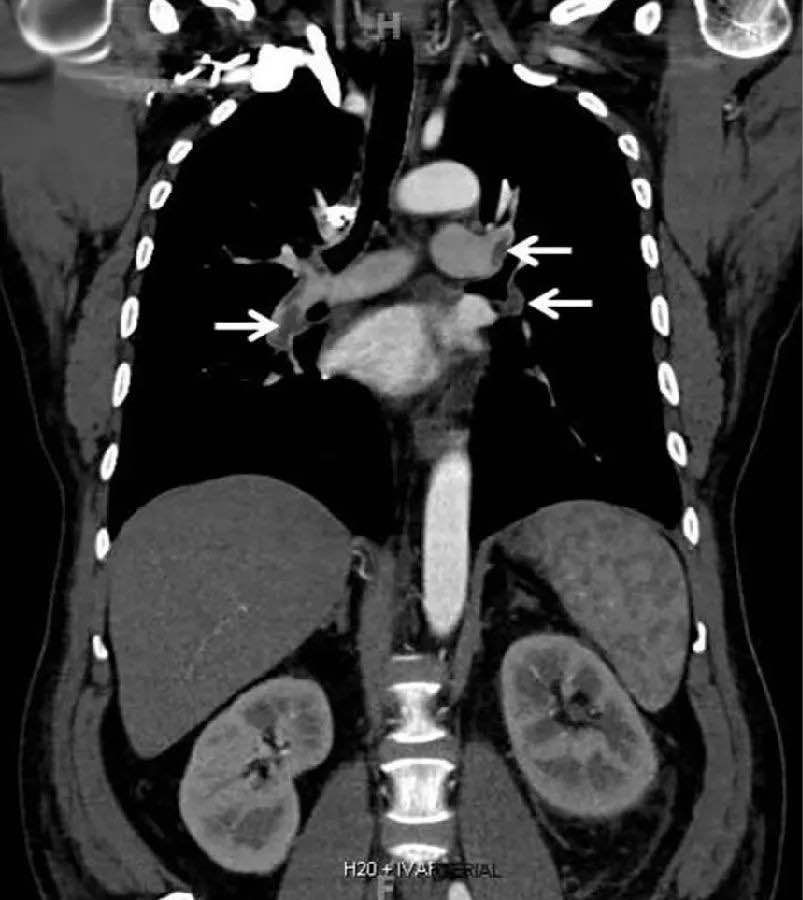

来源:患者胸部造影剂增强CT , 显示肺动脉栓塞